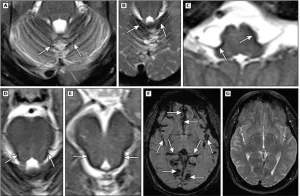

- For positive diagnosis: pathognomonic and highly sensitive T2* sequences → hemosiderin appears as a hypodense rim on the surface of the brainstem, cerebellum, spinal cord, and cerebral cortex. Lower sensitivity of FLAIR and T2 sequences (hypodensities) and T1 (frequently normal or rarely showing hyperintensities). No contrast enhancement.